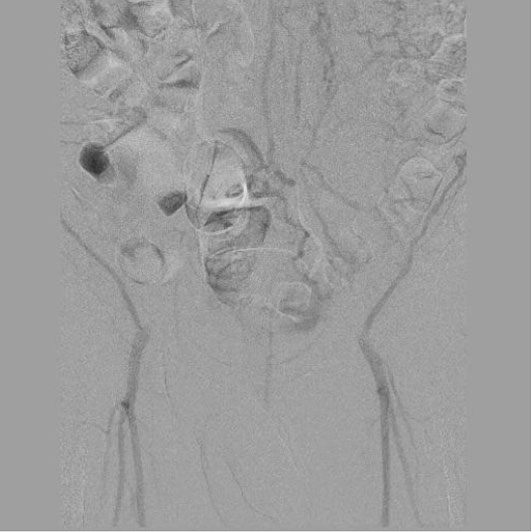

В ходе обследований было выявлено критическое поражение сосудов – ниже отхождения почечных артерий полная окклюзия (закупорка) брюшного отдела аорты, левой и правой подвздошных артерий. Кровоток к бедренным артериям и ниже доходил в недостаточном количестве, через обходные сосуды (коллатерали).

Пациенту была выполнена высокотехнологичная миниинвазивная эндоваскулярная операция – баллонная ангиопластика и стентирование брюшного отдела аорты, левой и правой подвздошных артерий, с хорошим результатом, с полным восстановлением прямого кровотока на всем протяжении обеих нижних конечностей. Данная операция миниинвазиваная, длилась 2.5 часа, была выполнена через 2 маленьких прокола в руке и ноге под местной анестезией и является альтернативой большой и долгой полостной операции, с разрезом брюшной полости под общим наркозом, которые чаще всего выполняются при таком сложном поражении.